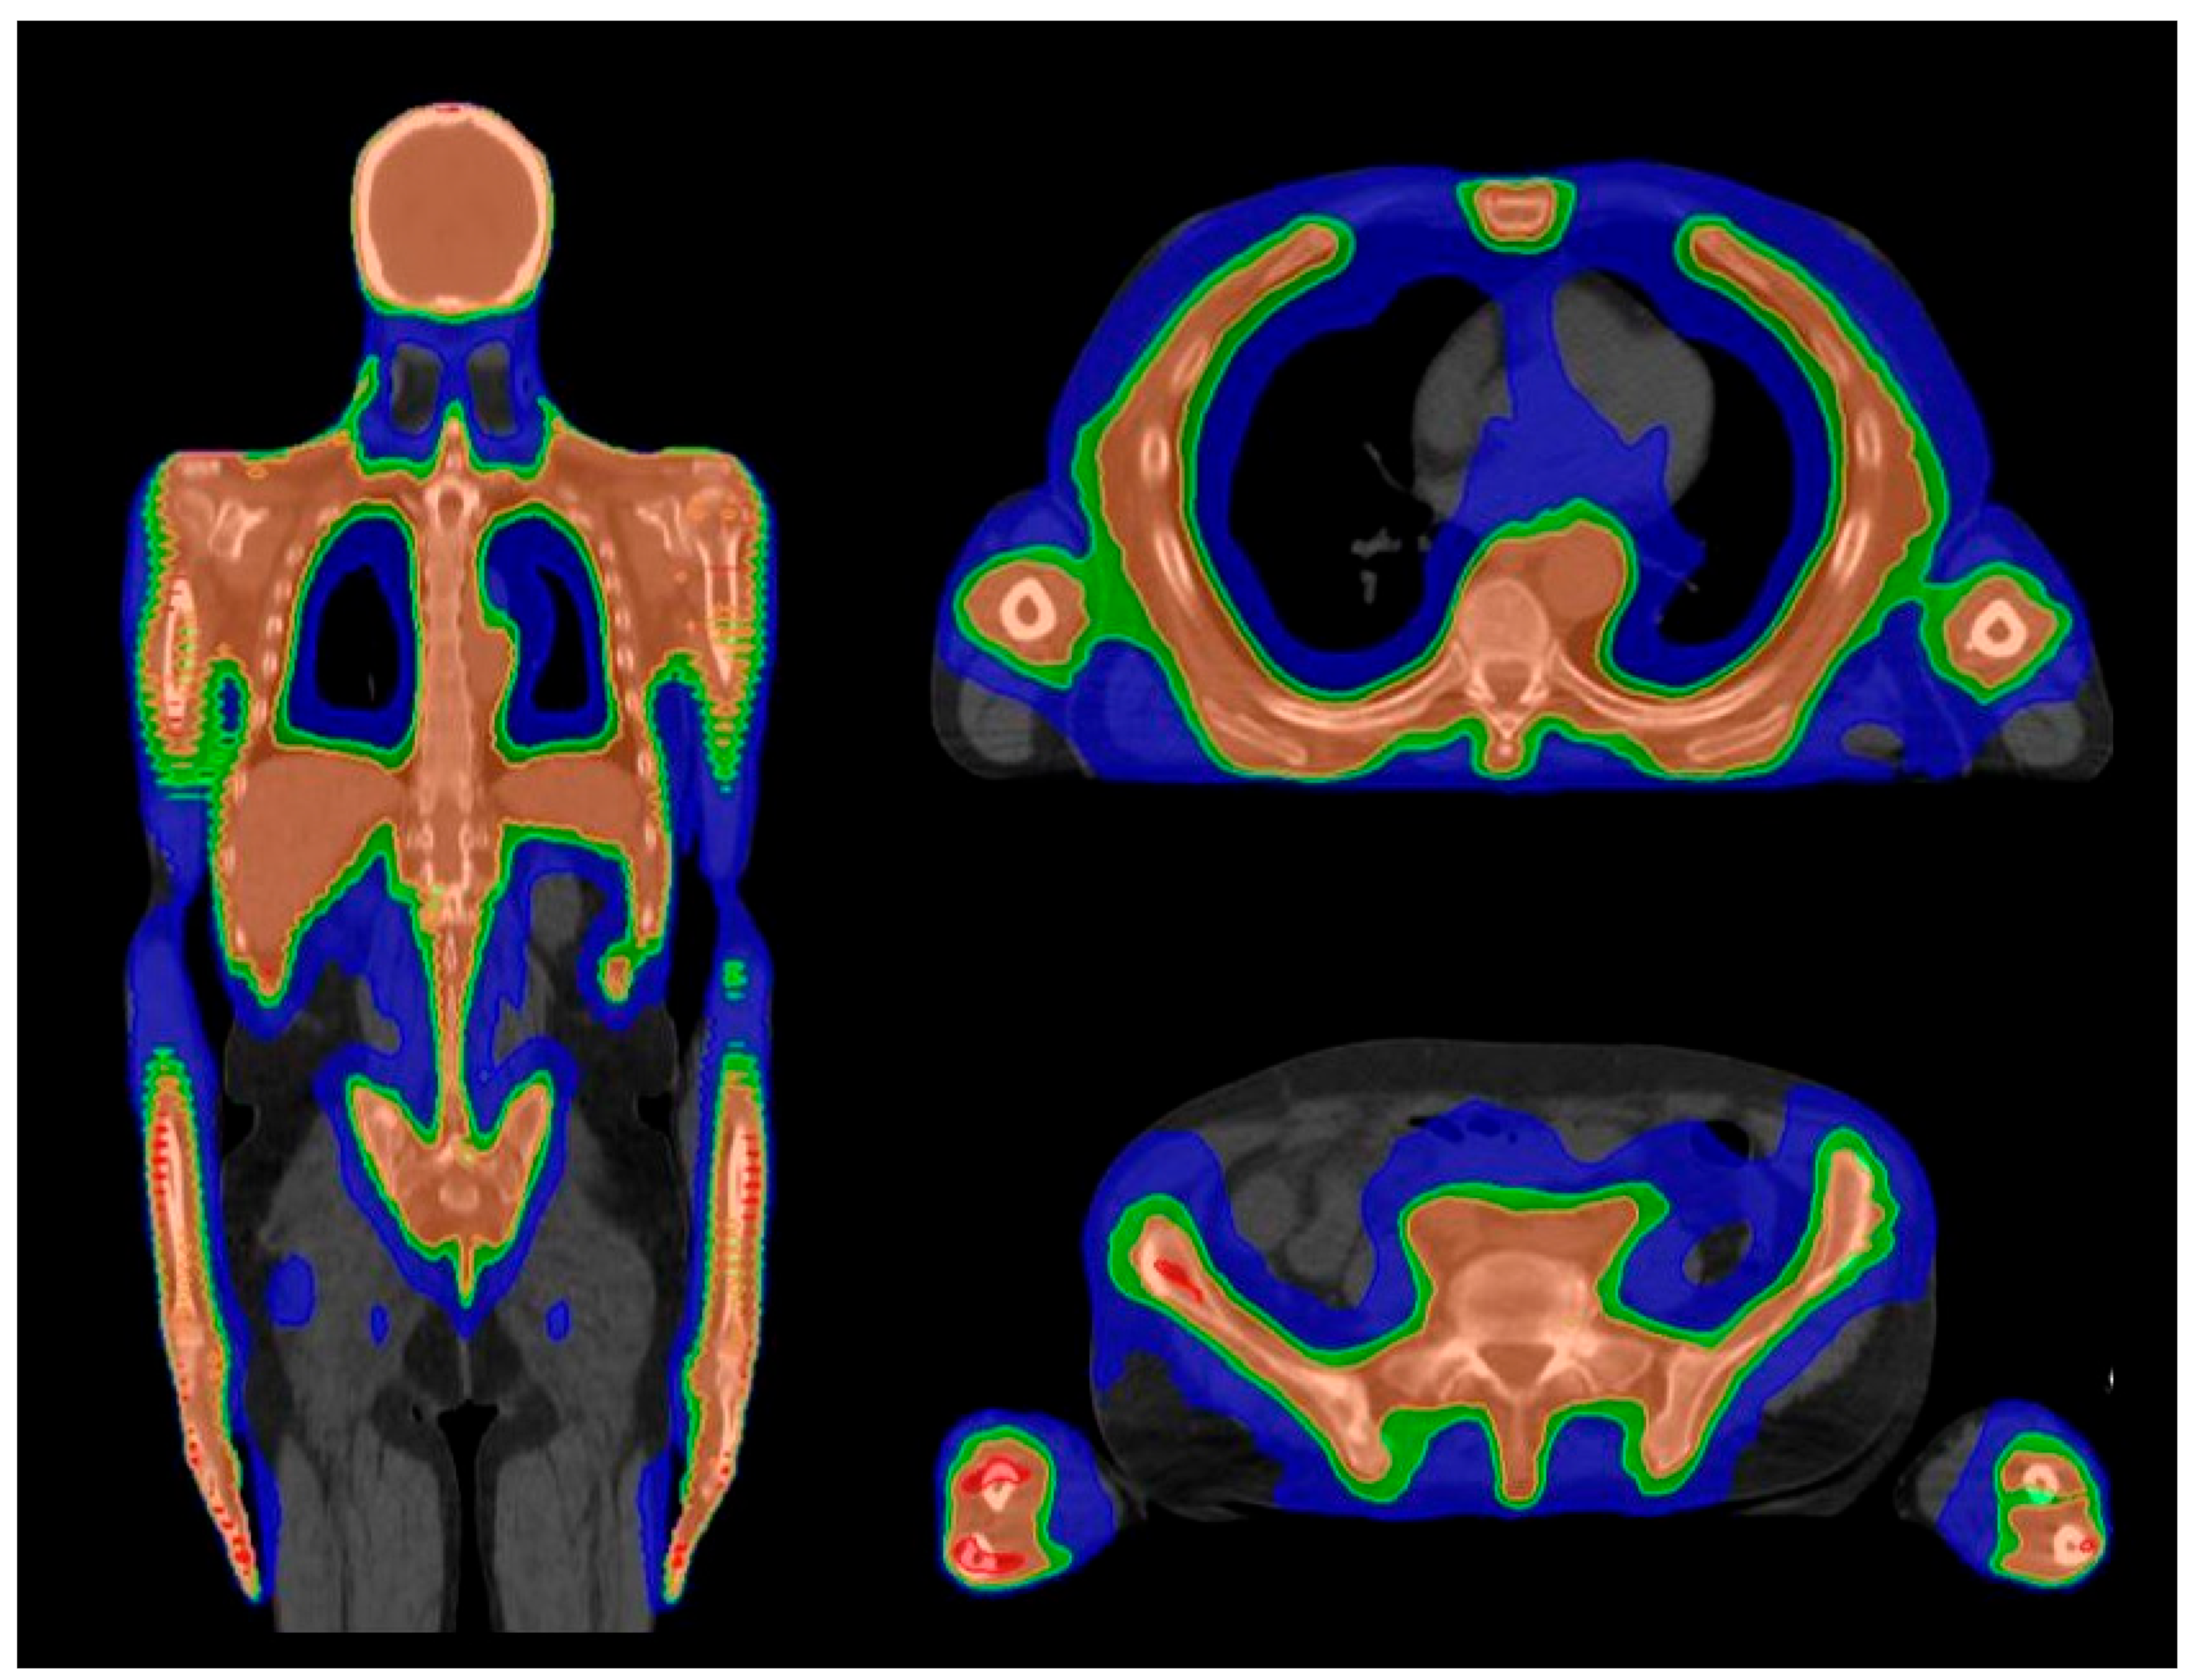

4.1. Planning

4.3. Treatment Delivery